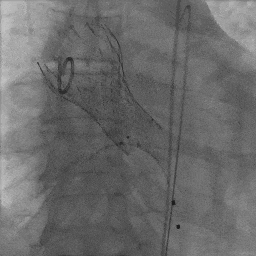

患者取平卧位,局麻镇静,颈内静脉置入中心静脉置管,测中心静脉压3cmH2O,左侧桡动脉穿刺置管监测动脉压力。术区无菌消毒铺巾,穿刺右侧桡动脉并置入6F鞘管,超声引导下穿刺双侧股动静脉,右股动脉预置两把Proglide缝合器,左侧股动静脉留置6F鞘管。将Lunderquist加硬导丝送至升主动脉,沿加硬导丝送20F GORE动脉鞘管。将临时起搏漂浮电极经右股静脉送至右室心尖部位,测试起搏器工作良好。予肝素6000单位,ACT大于250s。经左股动脉置入6F猪尾导管,在释放体位下行主动脉根部造影。经右侧桡动脉送脑保护装置分别在左颈总动脉、头臂干动脉释放保护。经右侧股动脉送入6F JL4.0造影导管造影提示:左前降支未见明显狭窄,TIMI血流III级;回旋支未见明显狭窄,TIMI血流III级。送入6F JR4.0造影导管造影提示:右侧冠脉未见明显狭窄,TIMI血流III级。在AL2导管指引下,直头导丝跨瓣至左心室,沿导丝送猪尾导管至左心室,测得跨瓣压差50mmHg。经猪尾导管送入塑形后的加硬导丝送至左心室内,沿加硬导丝送启明L26主动脉瓣系统至主动脉瓣处,在释放体位下释放至工作状态,经猪尾导管行主动脉造影示瓣膜定位良好。继续完全缓慢释放瓣膜。送入20×40mm球囊至主动脉瓣,在180次/分起搏下,收缩压下降至50mmHg时行球囊扩张,扩张无明显腰征。主动脉造影示瓣膜支架膨胀良好,微量瓣周漏。撤出输送系统。经胸超声评估主动脉瓣位为人工瓣回声,位置固定,瓣叶活动良好。主动脉造影提示主动脉无夹层、出血。行造影提示腹主动脉、髂动脉、股总动脉未见明显异常,缓慢撤出20F大鞘管,缝合右侧股动脉穿刺点,保留右侧临时起搏器并固定良好。

瓣膜植入后球囊后扩张

球囊扩张后主动脉根部造影